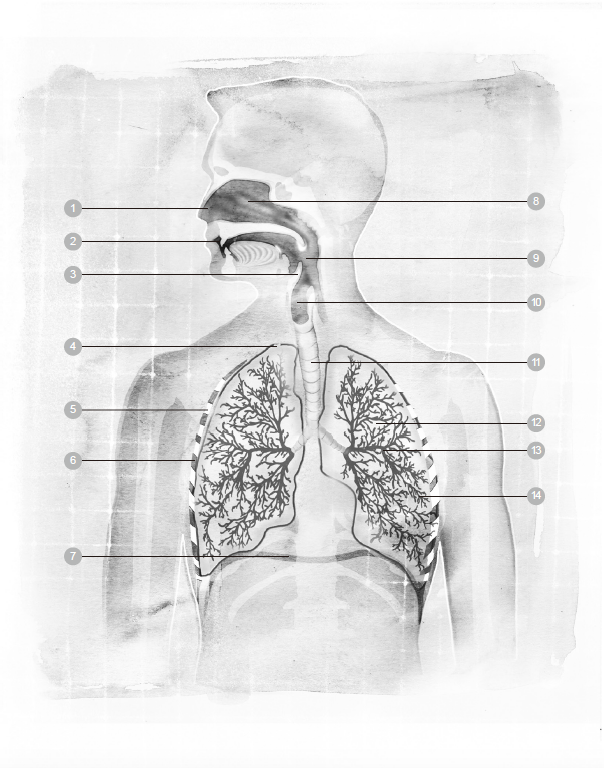

1 鼻子 6 肋间肌 11 气管

2 口 7 横膈膜 12 肺

3 会厌 8 鼻腔 13 支气管

4 胸膜 9 咽头(喉咙) 14 肺泡

5 肋骨 10 喉头